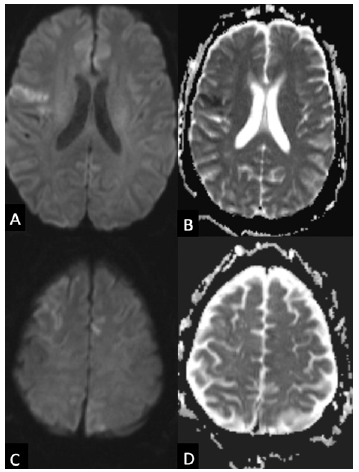

A 54-year-old male with a past medical history of atrial fibrillation status post ablation on therapeutic anticoagulation with rivaroxaban, recent mitral and tricuspid valve replacements, and heart failure with reduced ejection fraction presented to the emergency department from home with lightheadedness and left sided weakness that had resolved after four minutes. A stroke code was called secondary to report of left sided weakness. His initial neurologic examination was without evidence of focal abnormality with a National Institutes of Health Stroke Scale (NIHSS) of 0. Initial non contrast CT of the brain was without abnormality and CT angiogram of the head and neck was without significant stenotic disease or large vessel occlusion. Brain MRI was obtained and showed acute and subacute, multifocal ischemic infarcts concerning for a central embolic source (Figure 1 A-D). The patient was noted to be febrile to 101.7 F on initial vital signs, fostering concern for endocarditis considering recent valve replacements.

Figure 1:Initial MRI showing multifocal infarcts Axial diffusion weighted images (A, C) show cortical hyperintensities in multiple vascular territories with the apparent diffusion coefficient (B, D) showing decreased values and pseudo normalization suggesting acute and subacute multifocal infarcts.